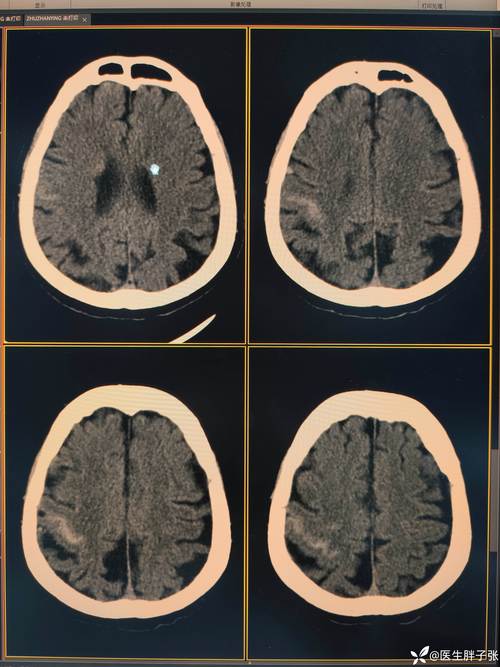

影像诊断区块链就是利用区块链技术,为医学影像(如CT、MRI、X光片等)及其诊断报告的生成、存储、传输、使用全过程建立一个去中心化、安全、透明、不可篡改的信任网络。